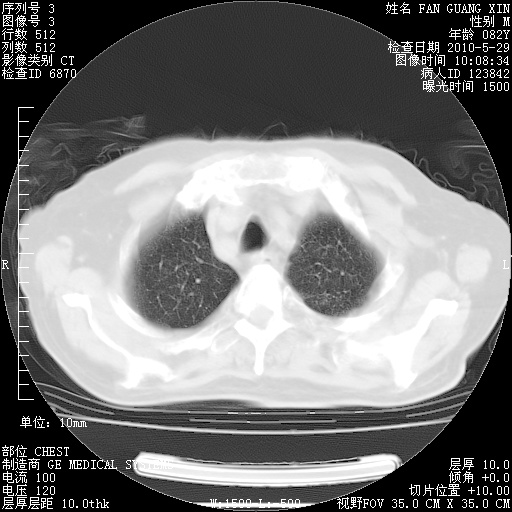

再治疗10天后的肺部CT

阅读此次胸部CT,肺间质渗出性改变较入院时有吸收。目前从体温、白细胞、中性分叶明显增高,肯定存在细菌感染(发生医院感染哦,若无消化道及泌尿系统等感染的依据,肺部感染可能大)。若你院头孢哌酮舒巴坦钠耐药率较高,同意你的方案,若48小时体温仍高,可考虑使用碳青霉稀类抗菌药物,同时可予超声雾化、注意滴数时加大液体量。白蛋白33.30g/L较低哦,需加强营养等支持治疗。